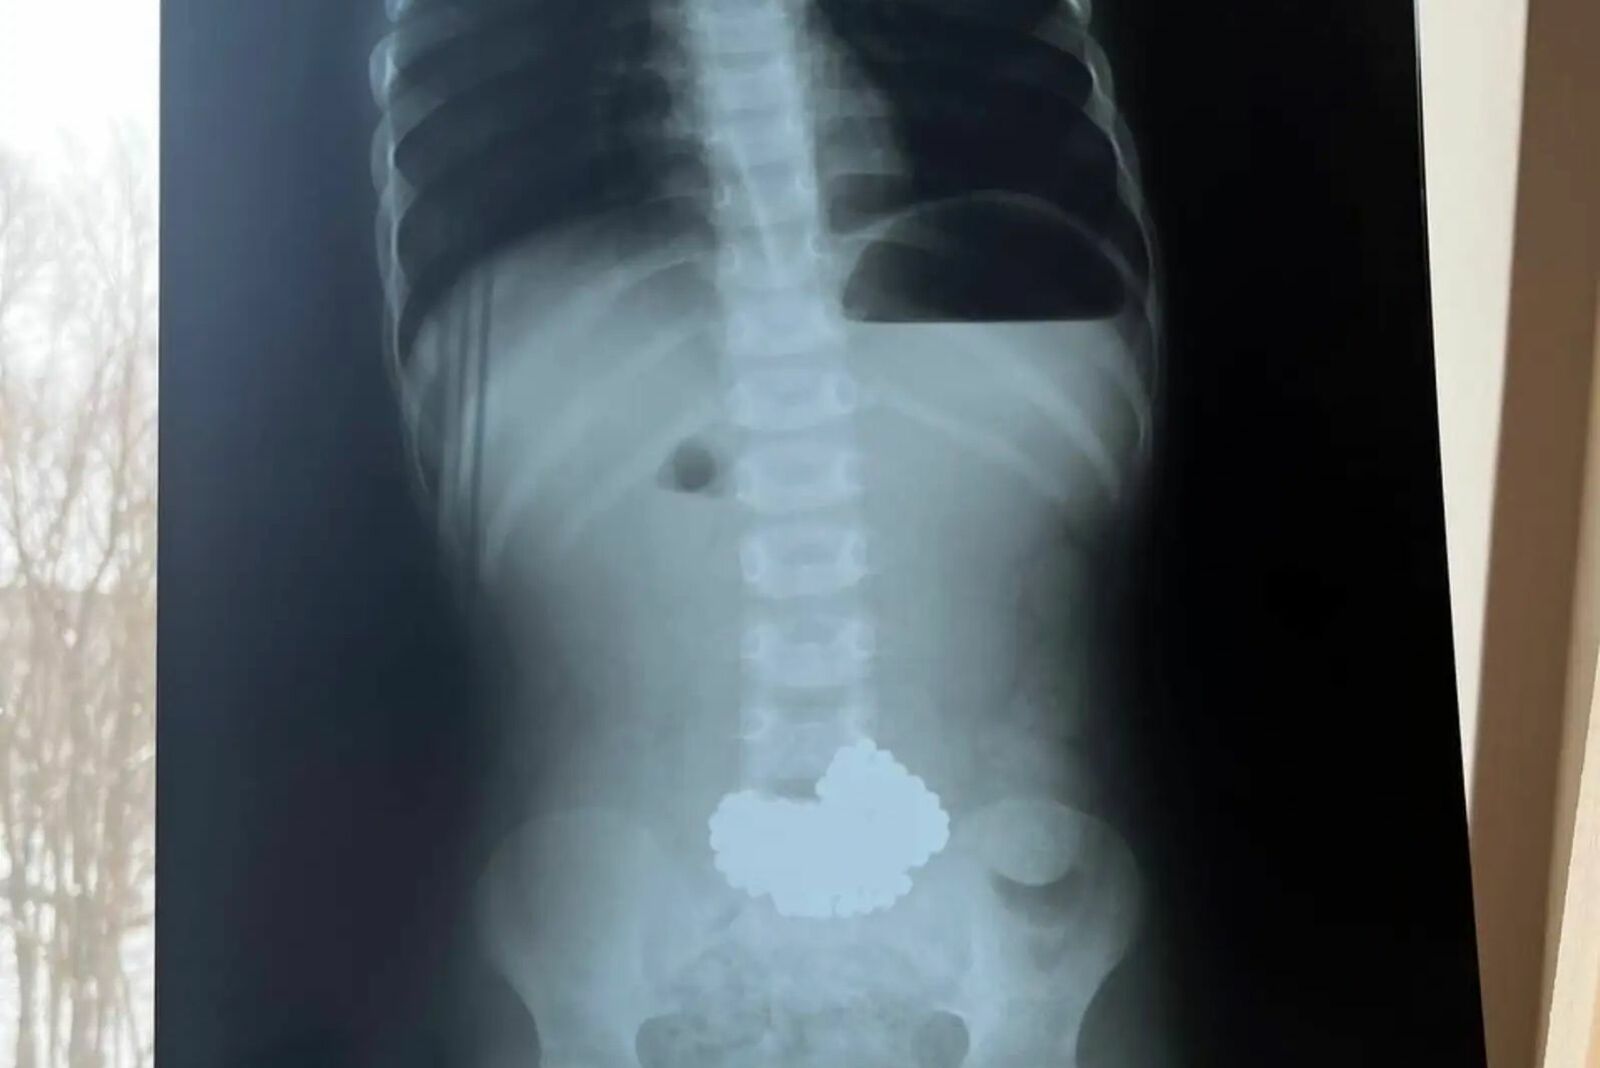

Ребёнок в Нефтекамске проглотил 206 шариков

Трёхлетнему мальчику попала в руки игрушка, состоящая из магнитных шариков. В итоге его срочно пришлось доставлять в Уфу санитарной авиацией. Малыш умудрился проглотить аж 206 круглых металлических предметов! Его жизни угрожала смертельная опасность.

Врачи приёмного покоя, куда привезли ребёнка, приняли решение о срочной транспортировке его в республиканскую клинику медицинским вертолётом. Уфимские коллеги оперативно провели хирургическое вмешательство и спасли юного пациента. Сейчас его жизни и здоровью ничего не угрожает. Родителям напоминают об опасности подобных игрушек. Попадая в петли кишечника, магнитные шарики притягиваются друг к другу. Это приводит к перфорации стенок, некрозам и заражению. Велика вероятность летального исхода. Будьте осторожны!